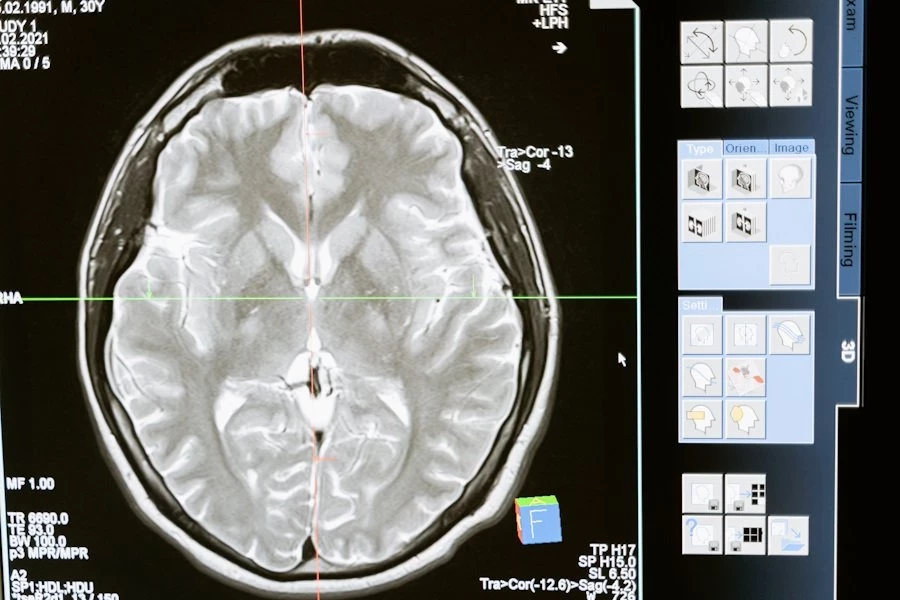

Исследователи выяснили, что чрезмерное употребление алкоголя в молодости может оставлять необратимые последствия в мозге, которые напоминают изменения, характерные для старения. Эти выводы опубликованы на портале Neurobiology of Aging.

После завершения "алкогольного периода" мышей оставили без спиртного до достижения ими возраста от 9 до 12 месяцев — это соответствует 30–40 годам у людей. Когда животных обследовали, выяснилось, что употребление алкоголя в молодом возрасте оставило след в их мозге. Нейронные связи функционировали хуже, что отражалось на передаче сигналов между нервными клетками. Подобные изменения часто сопровождают ухудшение памяти и когнитивных способностей у пожилых людей.